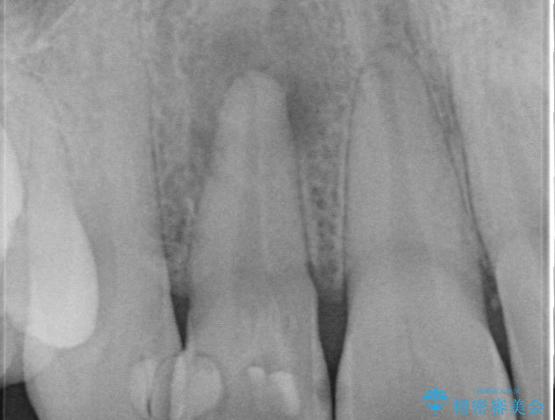

前歯が痛い。根管治療~セラミッククラウン

- 前歯が痛いことを主訴に来院されました。

顕微鏡やラバーダムを使用した根管治療を行ってくれる病院を探していたそうです。

根管治療を含め、オールセラミッククラウンにて修復治療を行っております。

当院の根管治療は100%ラバーダムを使い無菌的な処置に配慮して行っております。

今回は歯冠修復にe-maxプレスクラウンを使っています。